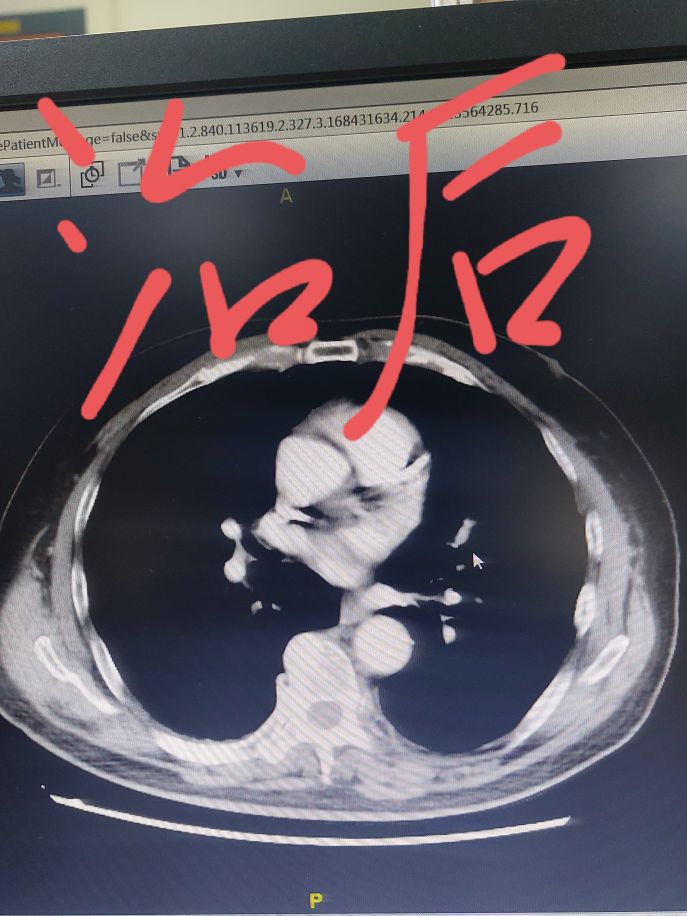

我给大家看一个具体的病例,这位患者几个月之前在我这里住院,当时左上肺有一个肿瘤,同时肺门纵隔淋巴结比较大,要说手术也不是不行,关键这位患者心脏还不好。这样的分期直接手术效果不太确定,所以我给他设计了先做两个周期药物治疗,然后再手术的策略。大家可以看一下下面的截图,通过穿刺这个患者病理是一个倾向于肺鳞癌,我给用的化疗加免疫药物的方案,进行了两个周期治疗,从我发的照片可以看到,做了两个周期治疗之后,肿瘤明显就减小了。

在治疗肿瘤的同时,心脏也在逐渐的调整恢复,这次达到了手术的要求,上周把手术给做了。手术后切下来的左上肺叶,我把肿瘤的位置剖开。肿瘤的位置流出来的都是那种棕黄色的像脓一样的东西,这是坏死的东西,当时我就给家属看,我说这个肿瘤细胞根据我的经验来看可能全被杀死了,咱们等等病理看看是不是这样。

这两天病理出来了,和我的判断一样,肺里的所有的肿瘤细胞被之前两个周期的化疗加免疫药物治疗完全杀死了,这个就称为病理学的完全缓解,再通过手术进行根治,那效果肯定是很好了。